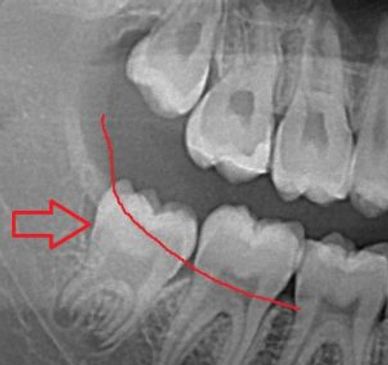

As wisdom teeth come in between the ages of 17 and 25, its best to monitor their growth and potential impact for not being able to come into place. Determination of when to remove wisdom teeth is NOT based on age, it is based on development of your jaws with respect to the wisdom teeth AND the developmental progress of the roots.

We recommend removal of wisdom teeth that have 1/2-3/4 root development that won't have enough space to come in. Wisdom teeth removal at this point is very quick with extremely low risk of complications. Because the surgery and anesthesia are separate jobs (versus one provider doing two jobs), the appointment for this is safer, always painless, and always memory-free on every patient, every time.